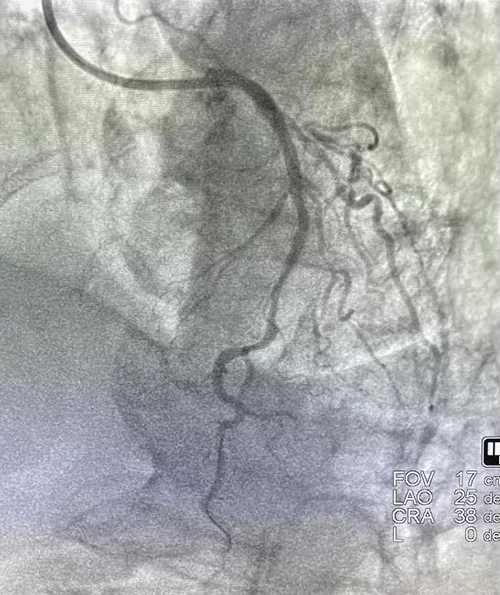

1月8日,山东第一医科大学附属省立医院(山东省立医院)心内科成功为一例严重冠脉钙化病变患者进行了准分子激光斑块消蚀术(ELCA),并顺利植入冠脉支架,腔内影像显示支架膨胀贴壁良好,未见夹层血栓。

术后